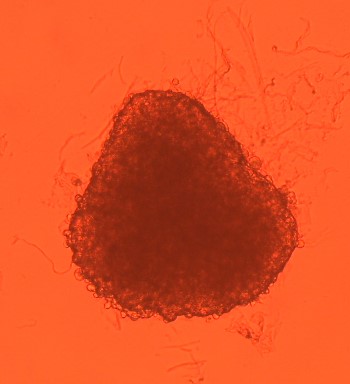

3D model pečene: v kvapkách visiacich z opačnej strany Petriho misky, sa bunky vplyvom gravitácie začnú zhlukovať a vytvoria štruktúru podobnú tkanivu v pečeni

V malej kvapke sa množia bunky pečeňového tkaniva. Unikátne zábery sú z nórskeho laboratória v NILU

Nosnou témou je aj vývoj, štandardizácia a validácia nových biologických modelov a metód, pomocou ktorých chceme odhaľovať mechanizmy vedúce k poškodeniu buniek čiže ku genotoxicite, mutagenite a karcinogenite a v konečnom dôsledku k vzniku ochorení, ako je napríklad rakovina. Modely, ktoré vyvíjame, sú predovšetkým z ľudských tkanív a sú to tzv. 3D (trojdimenzionálne) viacbunkové modely, ktoré pripomínajú mikrotkanivá alebo miniorgány. Ide o proces patriaci medzi tzv. NAMs (new approach methods), ktoré by mali zredukovať a časom aj úplne nahradiť experimenty na zvieratách. Spolu s inými vedeckými skupinami sme vyvinuli pľúcny model, model pečene a pracujeme na ďalších, ako model prsníka, gastrointestinálny model a pod. Takisto spolupracujeme na tzv. organ on chip, teda modeloch miniorgánov prepojených spolu tekutinou nahradzujúcou krv a pripomínajúcich miniorganizmus. Tieto modely sú stále vo vývoji, štandardizujeme ich a validujeme.

Mária Dušinská: V prvom rade, keď chceme testovať nanočastice alebo iné materiály, prípadne chemické látky, vychádzame z toho, v akom prostredí sa nachádzajú a ako môžu pôsobiť na ľudí. Rozlišujeme, či sa šíria vzduchom, vtedy aplikujeme pľúcny model alebo vodou a potravou, vtedy použijeme gastrointestinálny model. Ak prenikajú skúmané látky cez kožu (napríklad v prípade látok, ktoré majú byť súčasťou kozmetických prípravkov a krémov), vtedy použijeme kožný model a podobne. Máme rozsiahlu biobanku. Bunky máme hlboko zmrazené v tekutom dusíku. Pred začiatkom štúdie pripravíme modely tkanív tak, že začneme kultivovať vybrané typy buniek v špeciálnych podmienkach. Stimulujeme ich, aby vytvorili štruktúru podobnú štruktúre daného tkaniva alebo orgánu. Trvá to niekoľko dní až týždňov. Napríklad pri pľúcnom modeli napodobňujeme pľúca tým, že bunky kultivujeme na membráne. To znamená, že z hornej časti sú vystavené vzduchu a zo spodnej (bazálnej časti) sú v tekutine simulujúcej krv. Je to fascinujúce, ako sa bunky inak správajú, keď sú organizované v tzv. mikrotkanive, v porovnaní s klasickým dvojdimenzionálnym rastom prichyteným na Petriho miske.